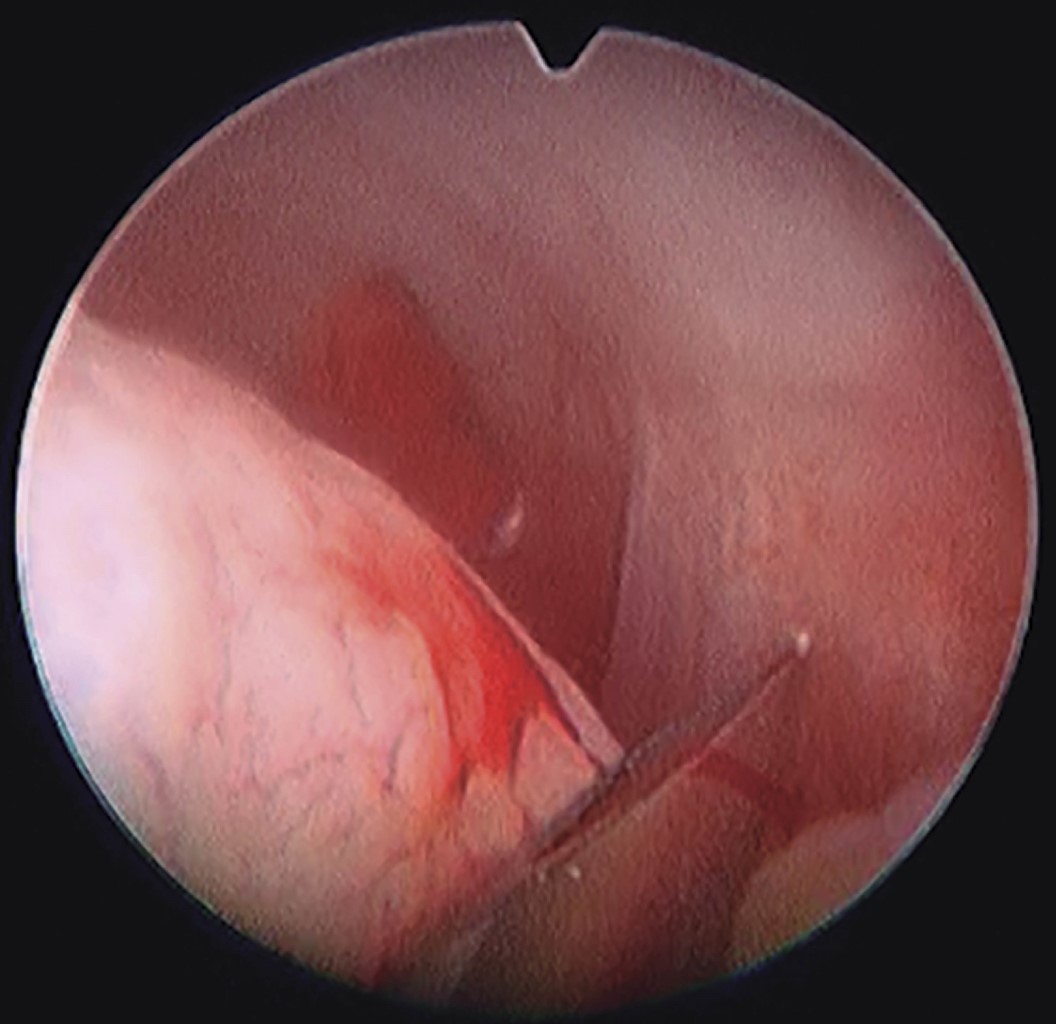

When positioning the arthroscope laterally, sometimes the translucency of the light is observed. The distance must be measured with the second working trocar to be able to deduce the position of our lens, this technique is called triangulation (Figure 12).15,16

This point will be the insertion place of the second route. A small incision can be made with a scalpel blade 11, and then with circular movements introduce the cannula with the sharp trocar. When observing the silhouette of the instrument on the monitor, it is time to change by blunt trocar. Must make sure to insert the entire sheath into our joint space, so as not to lose our cannula when replacing the instruments.

Through this second route we can introduce the tip of the ablation cutting system to perform the capsulotomy or myotomy of the pterygoid muscle. Once this is done, with a probe, you can navigate again to the posterior recess to reduce the position of the mandibular disc.